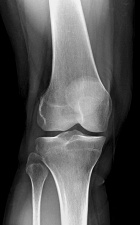

B.S. - 47 year old female with one year history of right knee pain, pain is posterior and is worse with activity, some relief with NSAID's